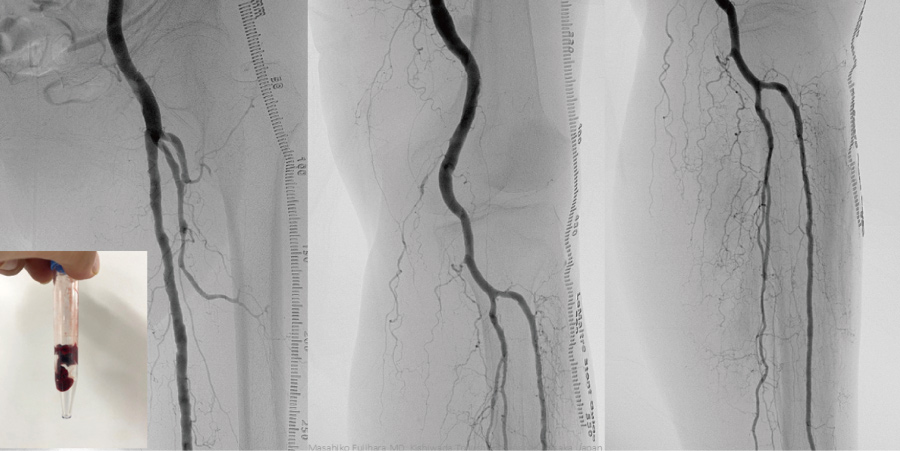

透析患者様にとって、シャントは生命線です。シャントは週3回、数時間使用しますが、バルーン拡張のみでは再び狭くなることも多く、3か月ごとなど定期的な治療が必要になる患者様もいます。私たちは、狭くなりにくい薬剤塗布型バルーンや人工血管を用いて、長い開存性を目標とした治療を行っています。この薬剤塗布型バルーンにおいては、国内で治験が行われた際、私も治験の責任者として参加しましたが、通常のバルーンと比べて長期間の効果を維持することが証明されています。

通常のバルーン

薬剤バルーン